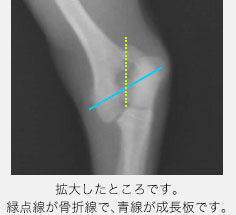

今回ご紹介する症例は5ヶ月齢のトイプードルで、散歩中に道路の側溝に落ちてから左前肢を挙げるとのことで来院されました。触診では左前肢の肘の部分を痛がり、レントゲン検査を行ったところ、左上腕骨の成長板骨折と分かりました。先ほどのSalter-Harris分類のType4で、成長板が斜めに折れていました。

青いラインが成長板です。数字が大きいほど後の障害が出やすいと言われています。 Type5は、強い圧力が加わることで成長板が機能しなくなるタイプです。